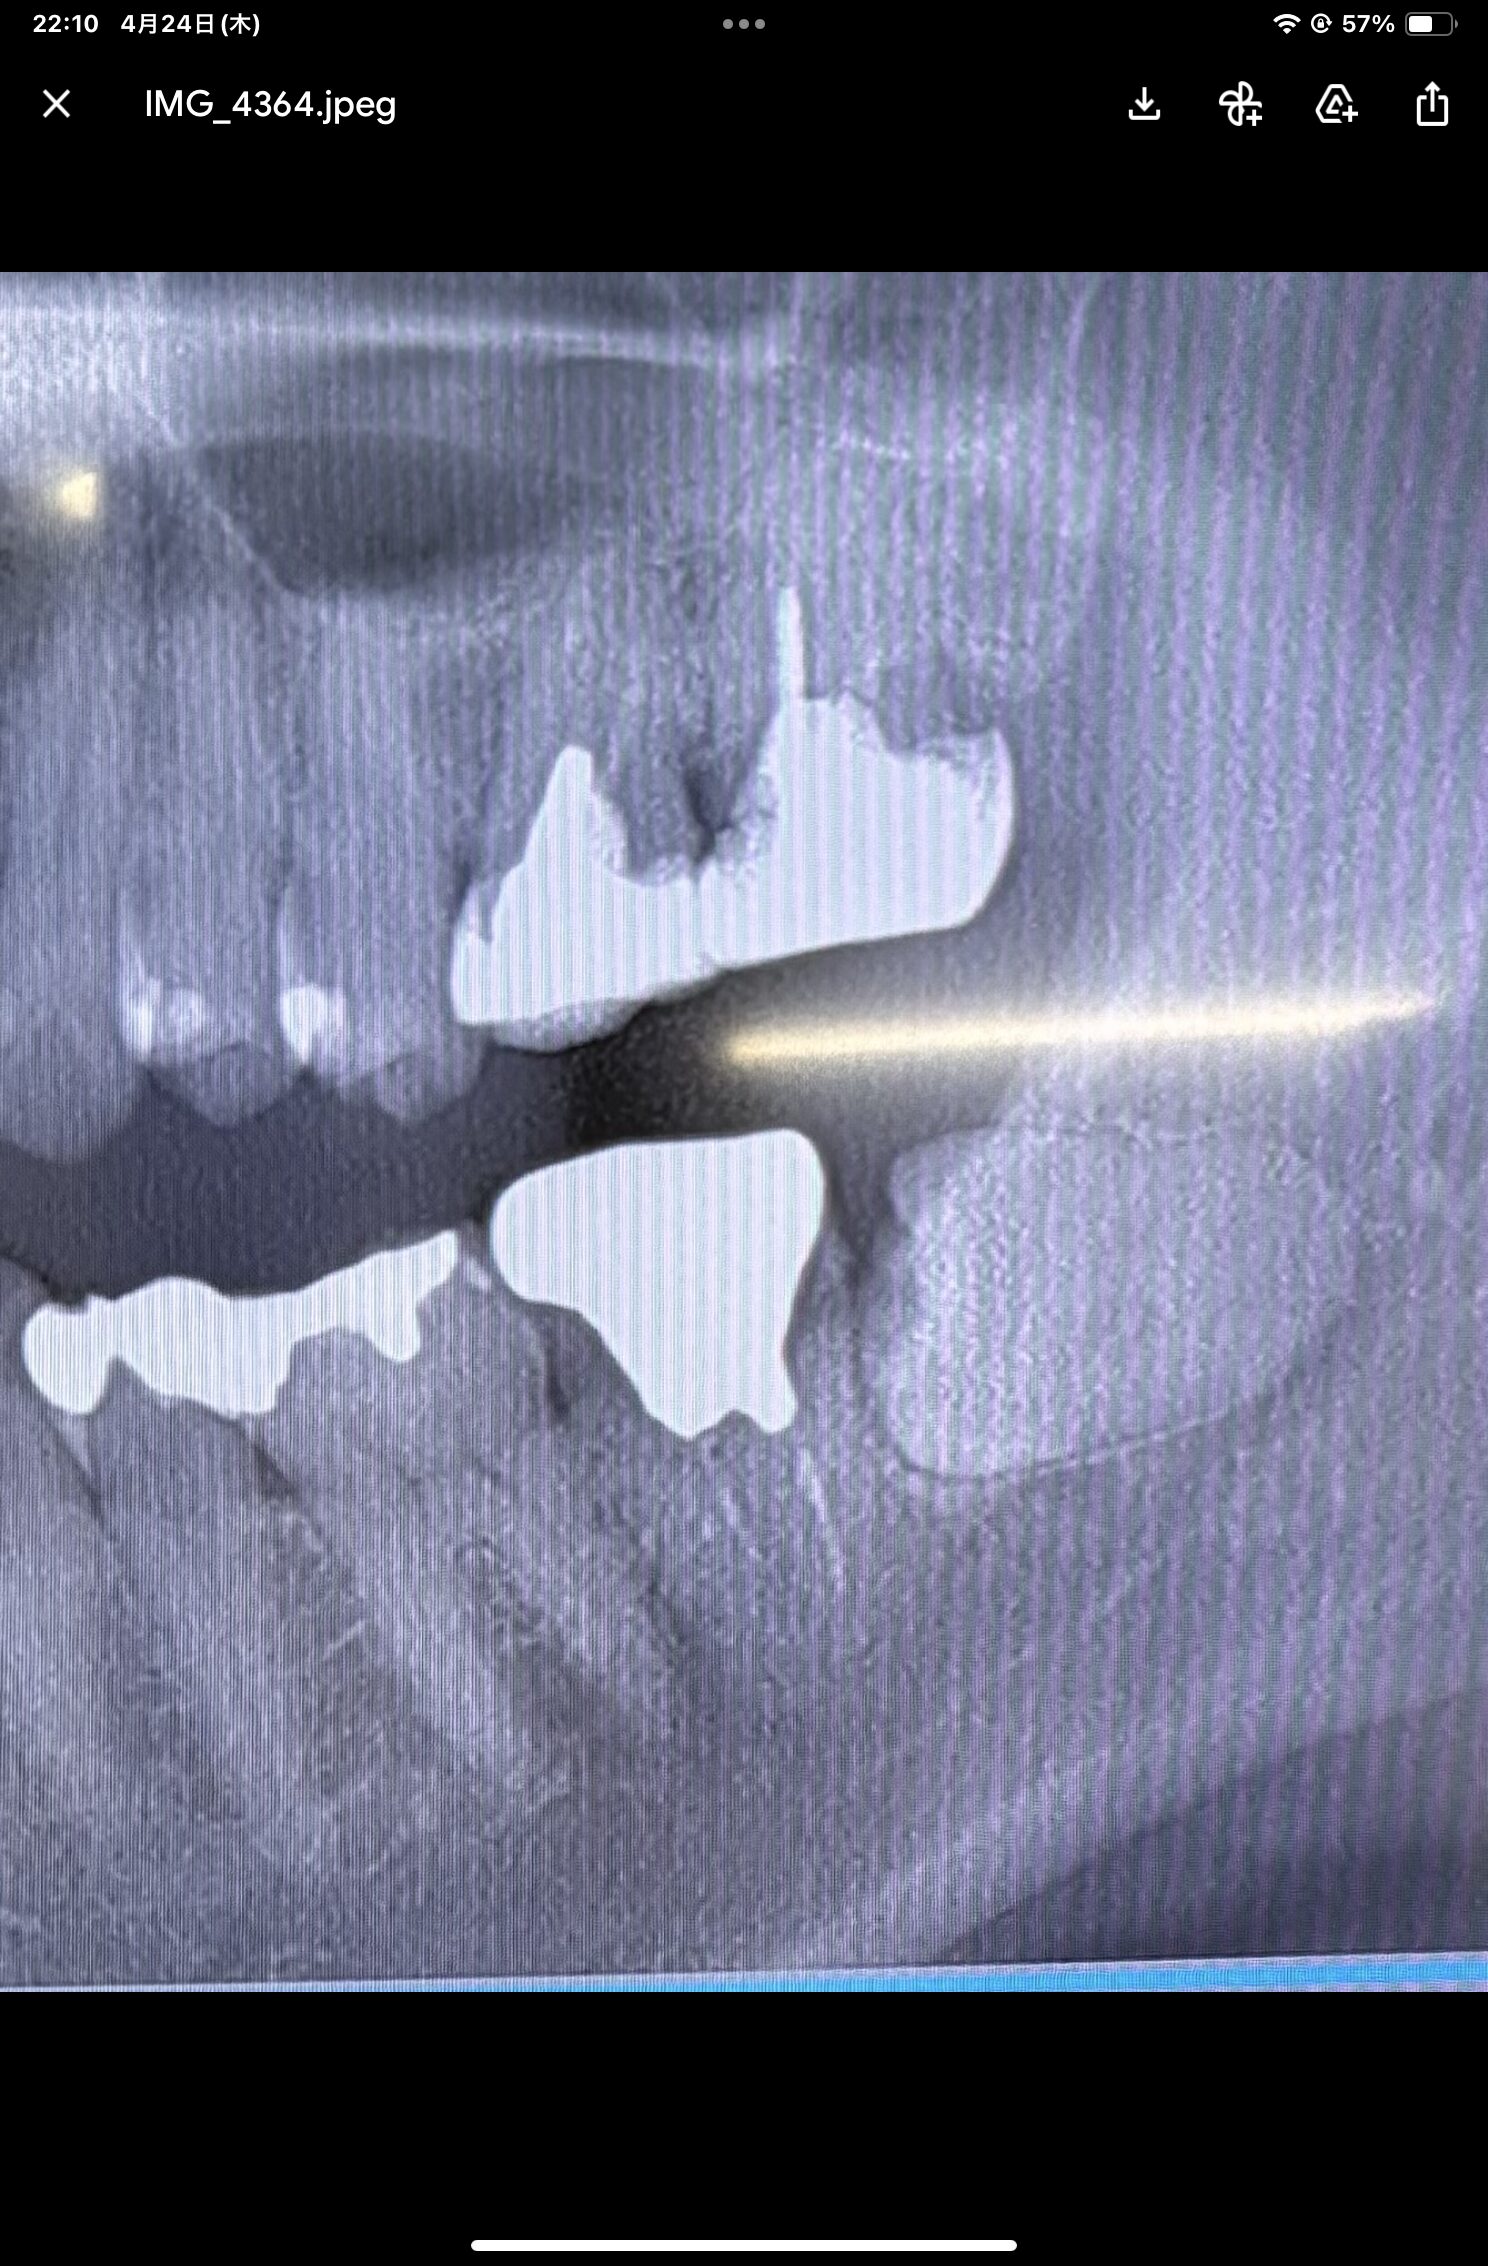

上記の様に下の親知らずが横向きに潜ってて神経が近いので、難抜歯になりますか?

麻痺が残るリスクはないでしょうか?